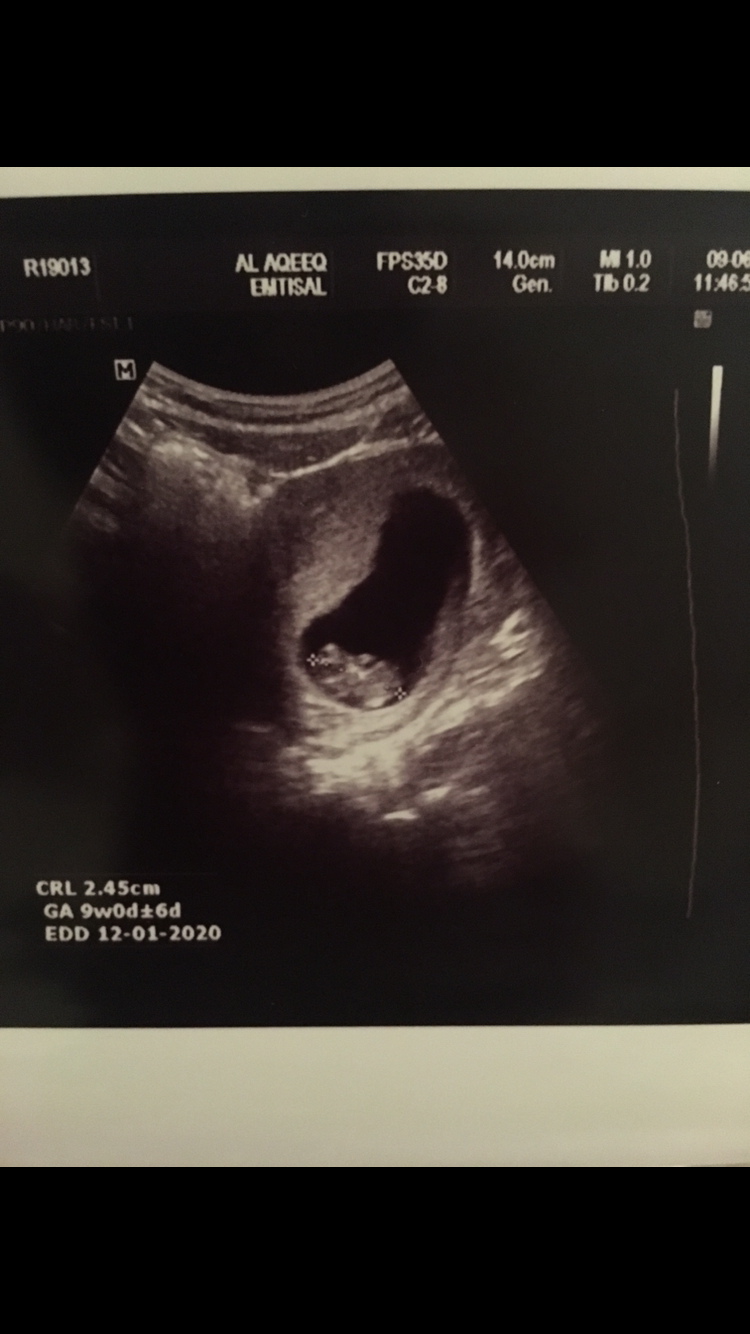

صبحهم بالخير 💜 موعد ولادتي المتوقع 2يناير الله يجعلها برداً وسلاماً علي وعلى كل حامل 🤲🏻 الجنس للآن مو اكيد نونيه الله ينبتها نباتاً حسناً ويسهل حملها ووضعها 👼🏻

السلام عليكم بنات النتدى الحلويين انا اردت ان اطلعكم على سر كيف تعرفين جنس مولودك بدون تكهنات وبالشهر الاول انا استشارية سونار كويتيه بصراحه خبره اقل من عشر سنوات ارفض ذكر اسمي وانا نادرا ما ادخل المنتدى عملت العديد من السونارات وكنت اركز على صور السونار لاعرف الفرق بين جنس البيبي المنتظر واكتشفت ان 99% ان لم يكن 100 % اذا كان راس الجنين ناحية اليمين فالجنين ذكر واذا كان رأس المولود ناحية اليسار فالجنين انثى ليس هناك فرق بين وحم البنت والولد ولا شكل البطن ولا حركة البيبي الوحم يختلف بناء على صحه الام قبل الحمل ونقص الفيتامينات اما شكل البطن يختلف حسب رشاقه الام اما الحركه فحسب صحه وسرعه نمو الجنين الان كل واحده تشوف سونارها وتاكد لي معلوماتي قبل نشرها بشكل فعلي بالرغم من تاكدي منها 100>#br### مقتبس .. و اذا تبغون الرابط عشان تقرأون الردود هذا هو 👇🏻 احس اني بديت اقتنع بكلامها و حابه اشوف رأيكم و سوناراتكم ! اذا توافق مع بحثها او لا !!

انا منزلة موضوع فيه صورة سوناري من اول

واتوقع ان الراس كان ع اليسار مو متاكدة

بنزل صورة لسوناري الاول هنا انا اتوقع انه الراس ع اليسار لان النونو مرا كان نقطه ف مايبين كويس وماعندي خبرة بالسونار

بس لما راجعت الفديو شفته كانه باليسار 🤔🙄